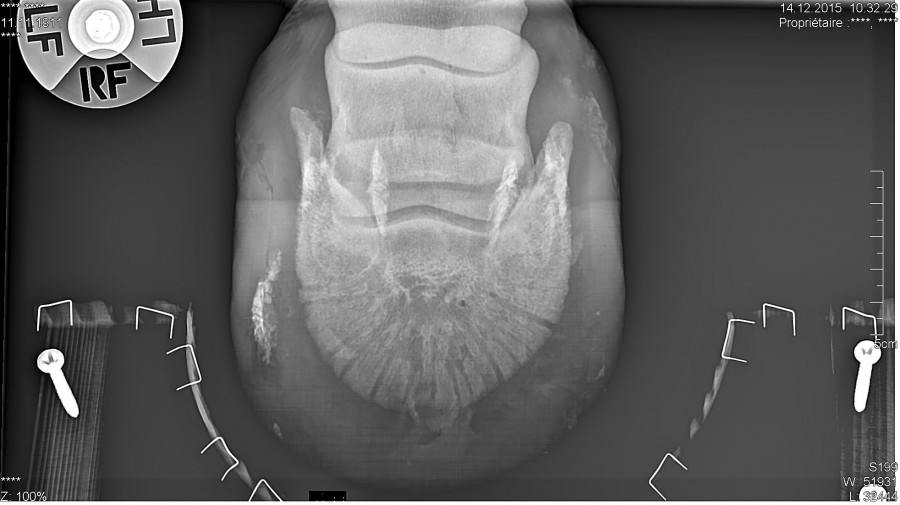

Pour ceux que ça intéresse, les radios :

Alors le verdict .... Une grosse fourmilière qui remontait très haut et qui décollait la paroie, ils ont charcuté tout ça, elle a un gros trou dans la paroie, ça va nécessiter des soins et du temps pour que ça repousse, mais au moins ce n'est pas un problème plus grave et chronique !

Il sonde le pied, qui est clairement la cause de la boiterie selon lui, et décide de faire une radio, malgré cela il n'arrive pas à localiser l'abcès, mais détecte, une petite déformation de la 3 ème phalange, pile à l'endroit ou l'espèce de bosse s'est formée dans la boîte cornée.